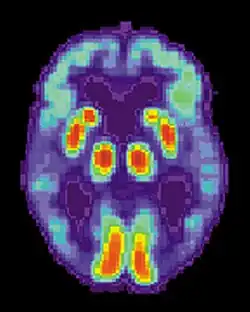

Neural systems used by procedural memory are commonly targeted by Human Immunodeficiency Virus; the striatum being the structure most notably affected.[64] MRI studies have even shown white matter irregularity and basal ganglia subcortical atrophy in these vital areas necessary for both procedural memory and motor-skill.[65] Applied research using various procedural memory tasks such as the Rotary pursuit, Mirror star tracing and Weather prediction tasks have shown that HIV positive individuals perform worse than HIV negative participants suggesting that poorer overall performance on tasks is due to the specific changes in the brain caused by the disease.[66]

Huntington's disease

Despite Huntington's disease being a disorder that directly affects striatal areas of the brain used in procedural memory, most individuals with the condition display different memory problems from people with striatum related brain diseases.[67] In more advanced stages of the disease, however, procedural memory is affected by damage to the important brain pathways that help the inner subcortical and prefrontal cortex parts of the brain to communicate.[68]